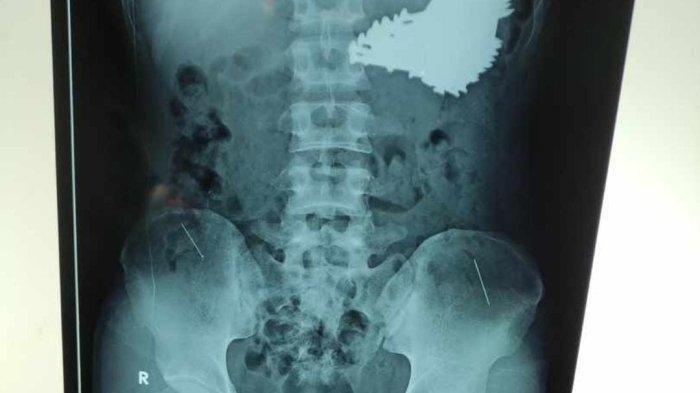

Setelah mendapatkan keterangan dari pihak keluarga, tim dokter lantas melakukan pemeriksaan radiologi dan rontgen terhadap Slamet.

Hasilnya, puluhan benda logam teridentifikasi di dalam lambungnya.

Angkat 70 paku dari perut pasien

Sementara itu, menurut Dokter spesialis bedah di RSUD Indramayu, dr. H. Rahmat, pihaknya berhasil mengangkat 70 batang paku dari dalam lambung pasien saat operasi yang berlangsung selama dua jam, pada Sabtu (22/6/2024).

“Kami langsung mengambil tindakan operasi selama dua jam,” ungkap Rahmat.

“Total ada sebanyak 70 batang paku,” pungkasnya. (*)